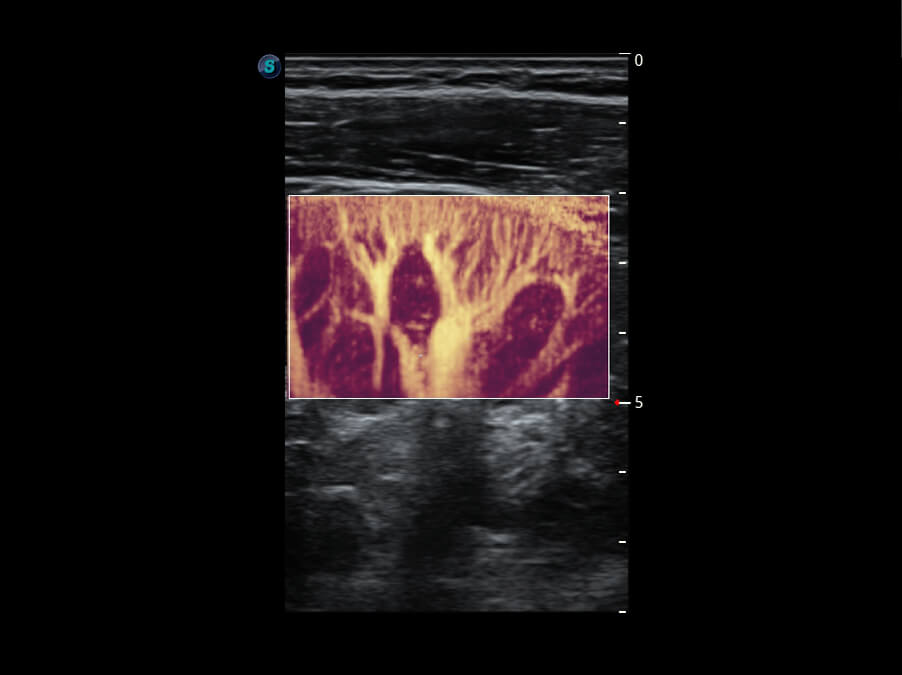

S60探头工艺,从前端信号处理每一个环节采集无损声学数据,真实还原组织原貌,再现解剖细节。

性能优异的硬件架构,极大提升超声系统的运行效率和数据处理能力。相比以往超声成像系统,Wis+平台为您带来极快的响应速度和成像帧频,提升检查流畅度。